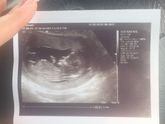

Ну вот и уже 12 неделек.... уже во всю идёт 13-ая. Токсикоза почти не осталось) и это радует. Теперь надо как то до жить до 1.06 будет скрининг))))))) хотя УЗИ было 26.05 все было в норме и малыша видела. Надеюсь может пол скажут!!!!!